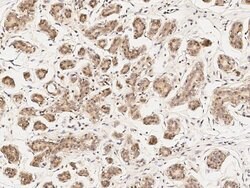

Invitrogen™ PKC delta Polyclonal Antibody

This product is preservative free. It is recommended to add sodium azide to avoid contamination (final concentration 0.05%-0.1%). This antibody has specificity for Human PRKCD.

The PKC family of serine/threonine kinases, including PRKCD (PKC delta), is activated intracellularly by signal transduction pathways. In humans, at least 12 different PKC polypeptides have been identified. These isoforms differ in primary structure, tissue distribution, subcellular localization, mode of action in vitro, response to extracellular signals, and substrate specificity. PKC alpha, beta I, beta II, and gamma form the conventional family; their activities are Ca2+- and phospholipid-dependent. Protein kinase C (PKC) can be activated by calcium and the second messenger diacylglycerol. PKC family members phosphorylate a wide variety of protein targets and are known to be involved in diverse cellular signaling pathways. PKC family members also serve as major receptors for phorbol esters, a class of tumor promoters. Each member of the PKC family has a specific expression profile and is believed to play distinct roles in cells. The protein encoded by this gene is one of the PKC family members. Studies both in human and mice demonstrate that this kinase is involved in B cell signaling and in the regulation of growth, apoptosis, and differentiation of a variety of cell types. Alternatively spliced transcript variants encoding the same protein have been observed.

| Immunohistochemistry (Paraffin), Western Blot, Immunocytochemistry | |

| A synthetic peptide corresponding to the C-terminus of the Human PRKCD. | |

| Human | |